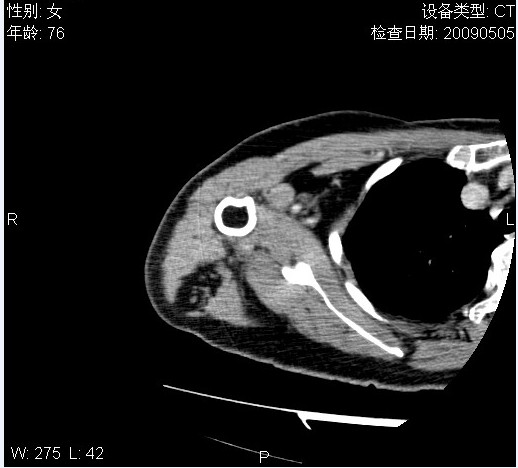

标题: CT19811:女,76岁,右上臂肿物1个月 [打印本页]

标题: CT19811:女,76岁,右上臂肿物1个月

使用了造影剂,可惜效果不太好

右肱骨上段软组织内见梭形低密度影,边界清楚,最长径约54mm.

病理结果:脂肪瘤。术中见肱骨骨膜受侵,有出血,量不详。

当时诊断意见:右肩三角肌内蔓状血管瘤(先天性动静脉瘘)。

本人对病理结果有个疑问:单纯的脂肪瘤内为什么有条状软组织影,那应该脂肪肉瘤才对啊?

该病例增强效果欠佳,由于经验欠缺,我们注射对比剂是由下肢足背静脉给药。注速2.0。虽然如此,但我们可以看到肿块内部条状软组织影是强化的,而且是连续的,并可见供血动脉是由腋动脉的其中一支即肩胛下动脉分出。从这些征象我们可以得出诊断:蔓状务血管瘤。

可病理偏偏为脂肪瘤,我怀疑取材有问题。因为蔓状血管瘤异常扩张的静脉外周是脂肪成分,它可以侵犯肌组织及骨骼。当取材于外周,那当然是脂肪瘤。此时我认为临床的最终诊断不应单从病理出发,应该综合考虑。